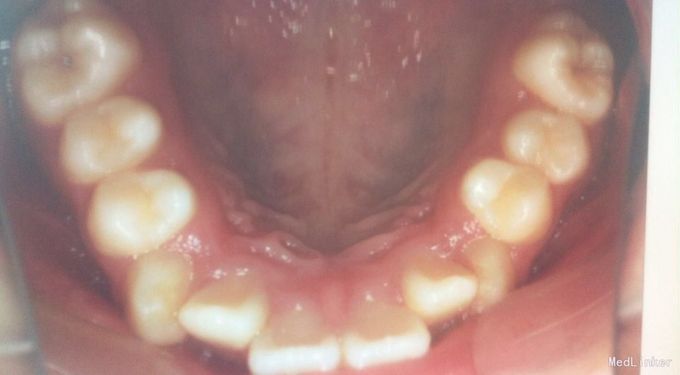

检查:恒牙期 右侧磨牙远中关系,左侧磨牙中性关系 前牙一度深覆合,正常覆盖 32、42未见 13、23唇侧错位 张口型异常 中线左偏约2mm 口腔卫生一般 X线未见32、42牙胚,28、38、48牙胚存在

诊断:安氏三类,先天缺牙 处理:拔牙矫治,直丝弓矫治器,拔除15、25,排齐整平上下牙列,关闭拔牙间隙,矫治后磨牙中性关系,前牙覆合覆盖正常,维持现有面型。